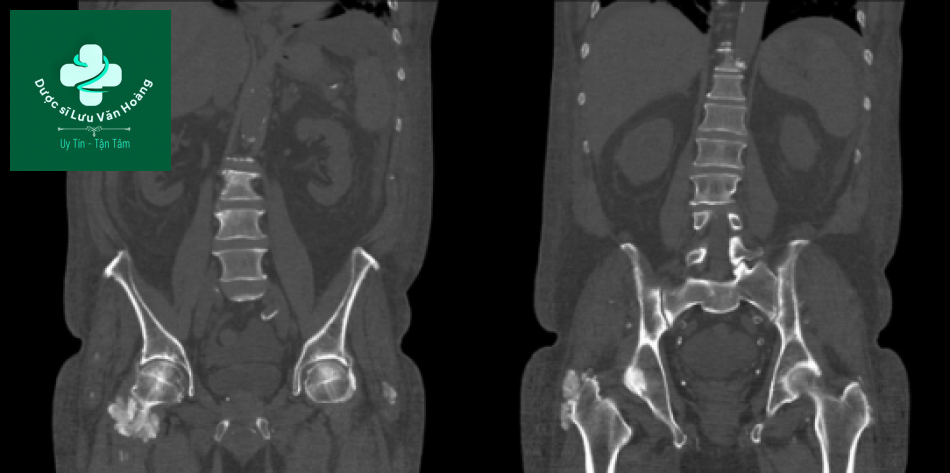

Bệnh nhân nam 45 tuổi suy thận và đã được ghép thận, có bất thường trong xét nghiệm sinh hóa máu. Phim chụp có hình ảnh rugger jersey spine và hình ảnh thận ghép nằm ở khung chậu.